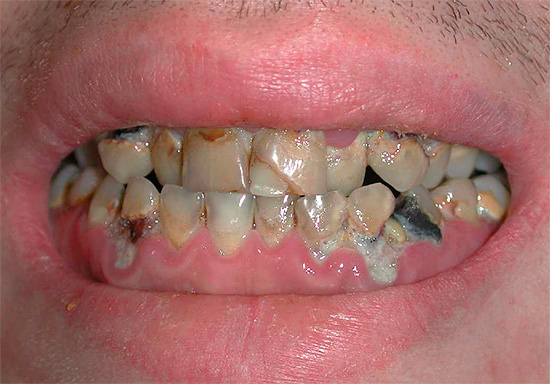

Ad esempio, nella foto sotto - carie generalizzata:

E questa foto mostra un altro esempio di come i denti sono stati colpiti carie generalizzata. Questa è una forma molto pericolosa della malattia, che minaccia una persona con la perdita di una parte significativa dei denti, la depulpazione (rimozione dei nervi) e l'installazione di corone: